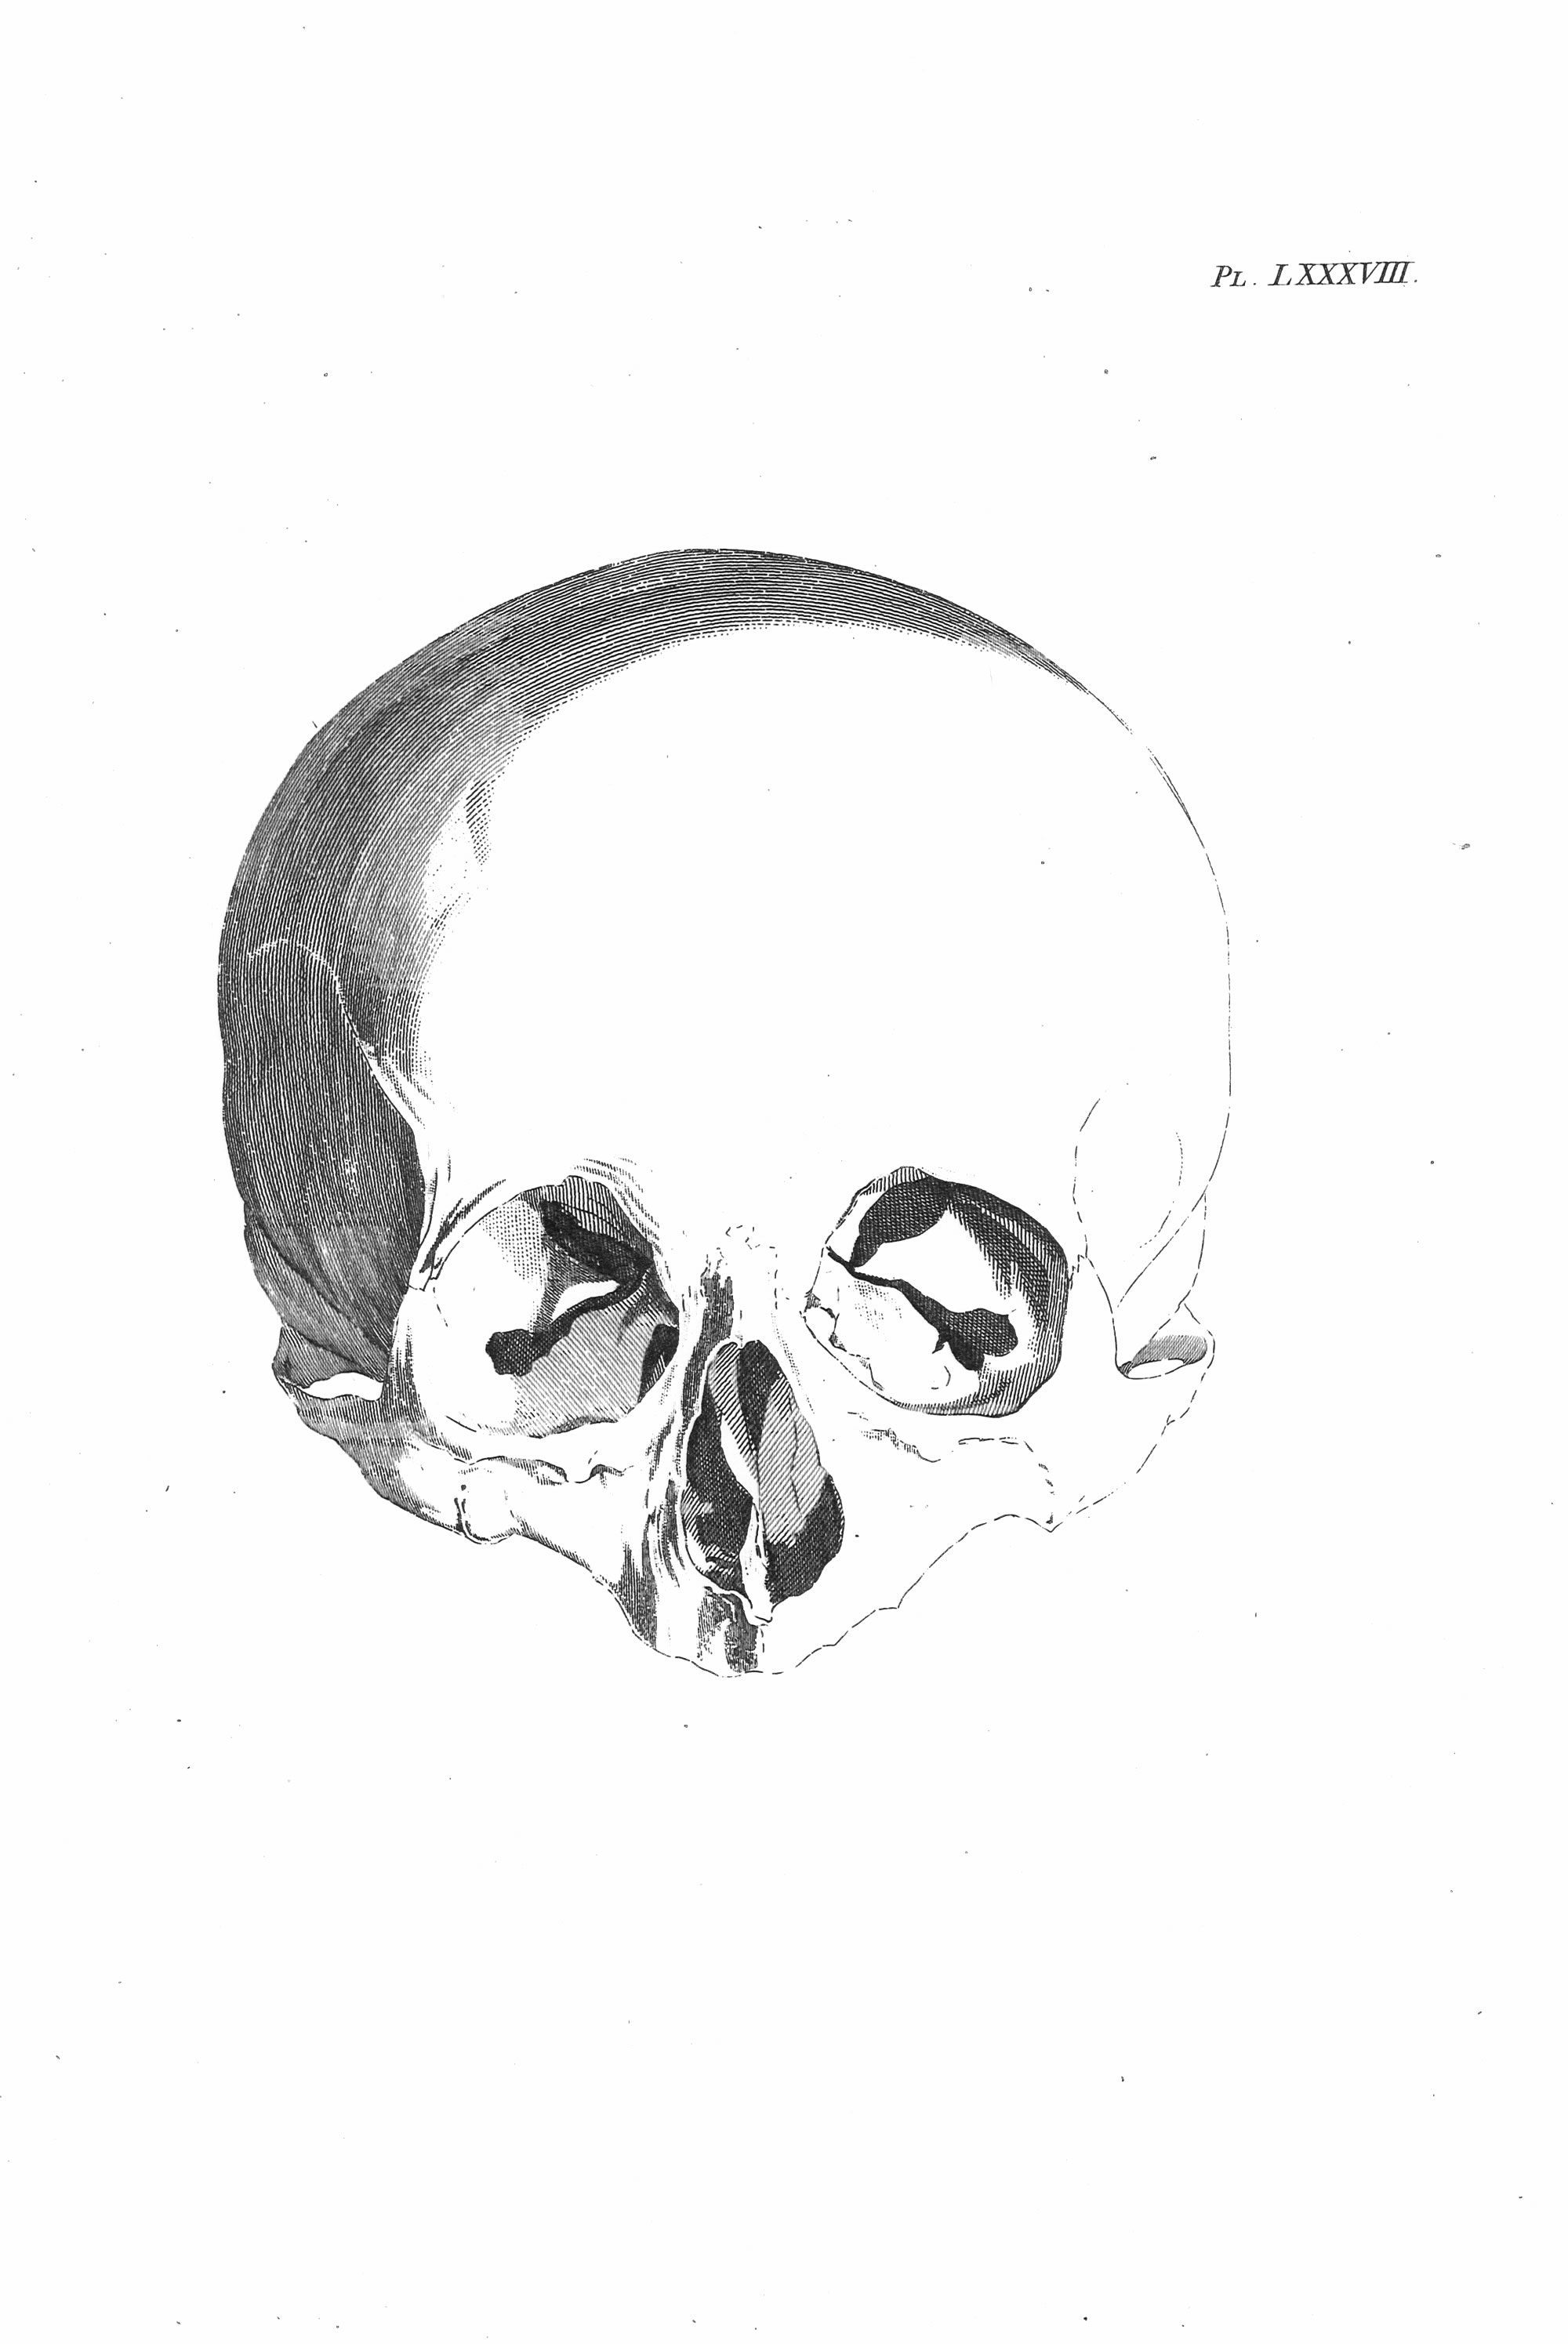

Gall: Plates

Gall, F. J. (1818). Anatomie et physiologie du système nerveux en général, et du cerveau en particulier, Avec des observations sur la possibilité de reconnoître plusieurs dispositions intellectuelles et morales de l´homme et des animaux, par la configuration de leurs têtes.

Librairie Grecque-Latine-Allemande, Vol. 3, I-XXXV u. 1-379 100 planches.